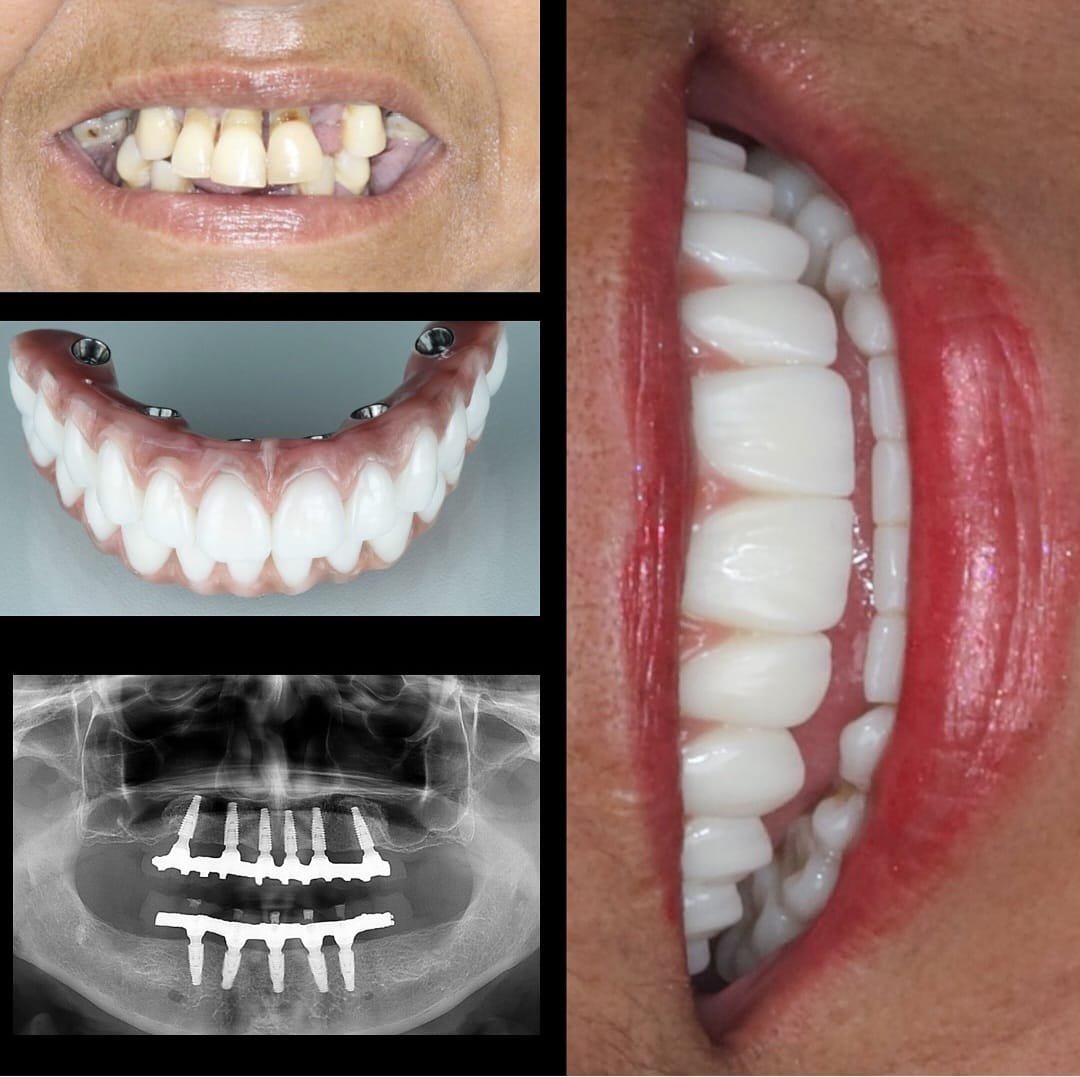

A Prótese Dentária é um dente artificial que substitui o dente natural perdido, devolvendo sua autoestima e conforto. O objetivo da Prótese Dentária é recuperar a plena função mastigatória e estética do paciente.

Há alguns anos, era comum o uso de dentaduras móveis, que causavam constrangimento e insegurança. Atualmente, com a Prótese Dentária, é possível utilizar de forma fixa e bastante confortável.

Os tipos de Prótese Dentária podem ser: Prótese Fixa, Removível e Prótese sobre Implantes(s).